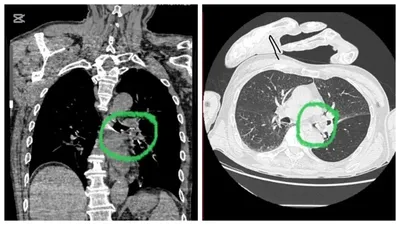

"Науқастың сол жақ негізгі кеңірдегінен көлемі 2х1,5 см алма кесегі табылды, ол тыныс жолын толықтай жауып тастаған. Жағдайды күрделендірген қосымша дерттері де болды: 1995 жылы өткен ми қан айналымының жіті бұзылуының салдары, дизартрия, сол жақ гемипарез, сондай-ақ III дәрежелі артериялық гипертензия", - деп хабарлады Алматы көпсалалы клиникалық ауруханасы.

Ота бөлмесінде маман интубациялық наркозбен видеобронхоскоп аппараты арқылы бөгде затты алып тастады.